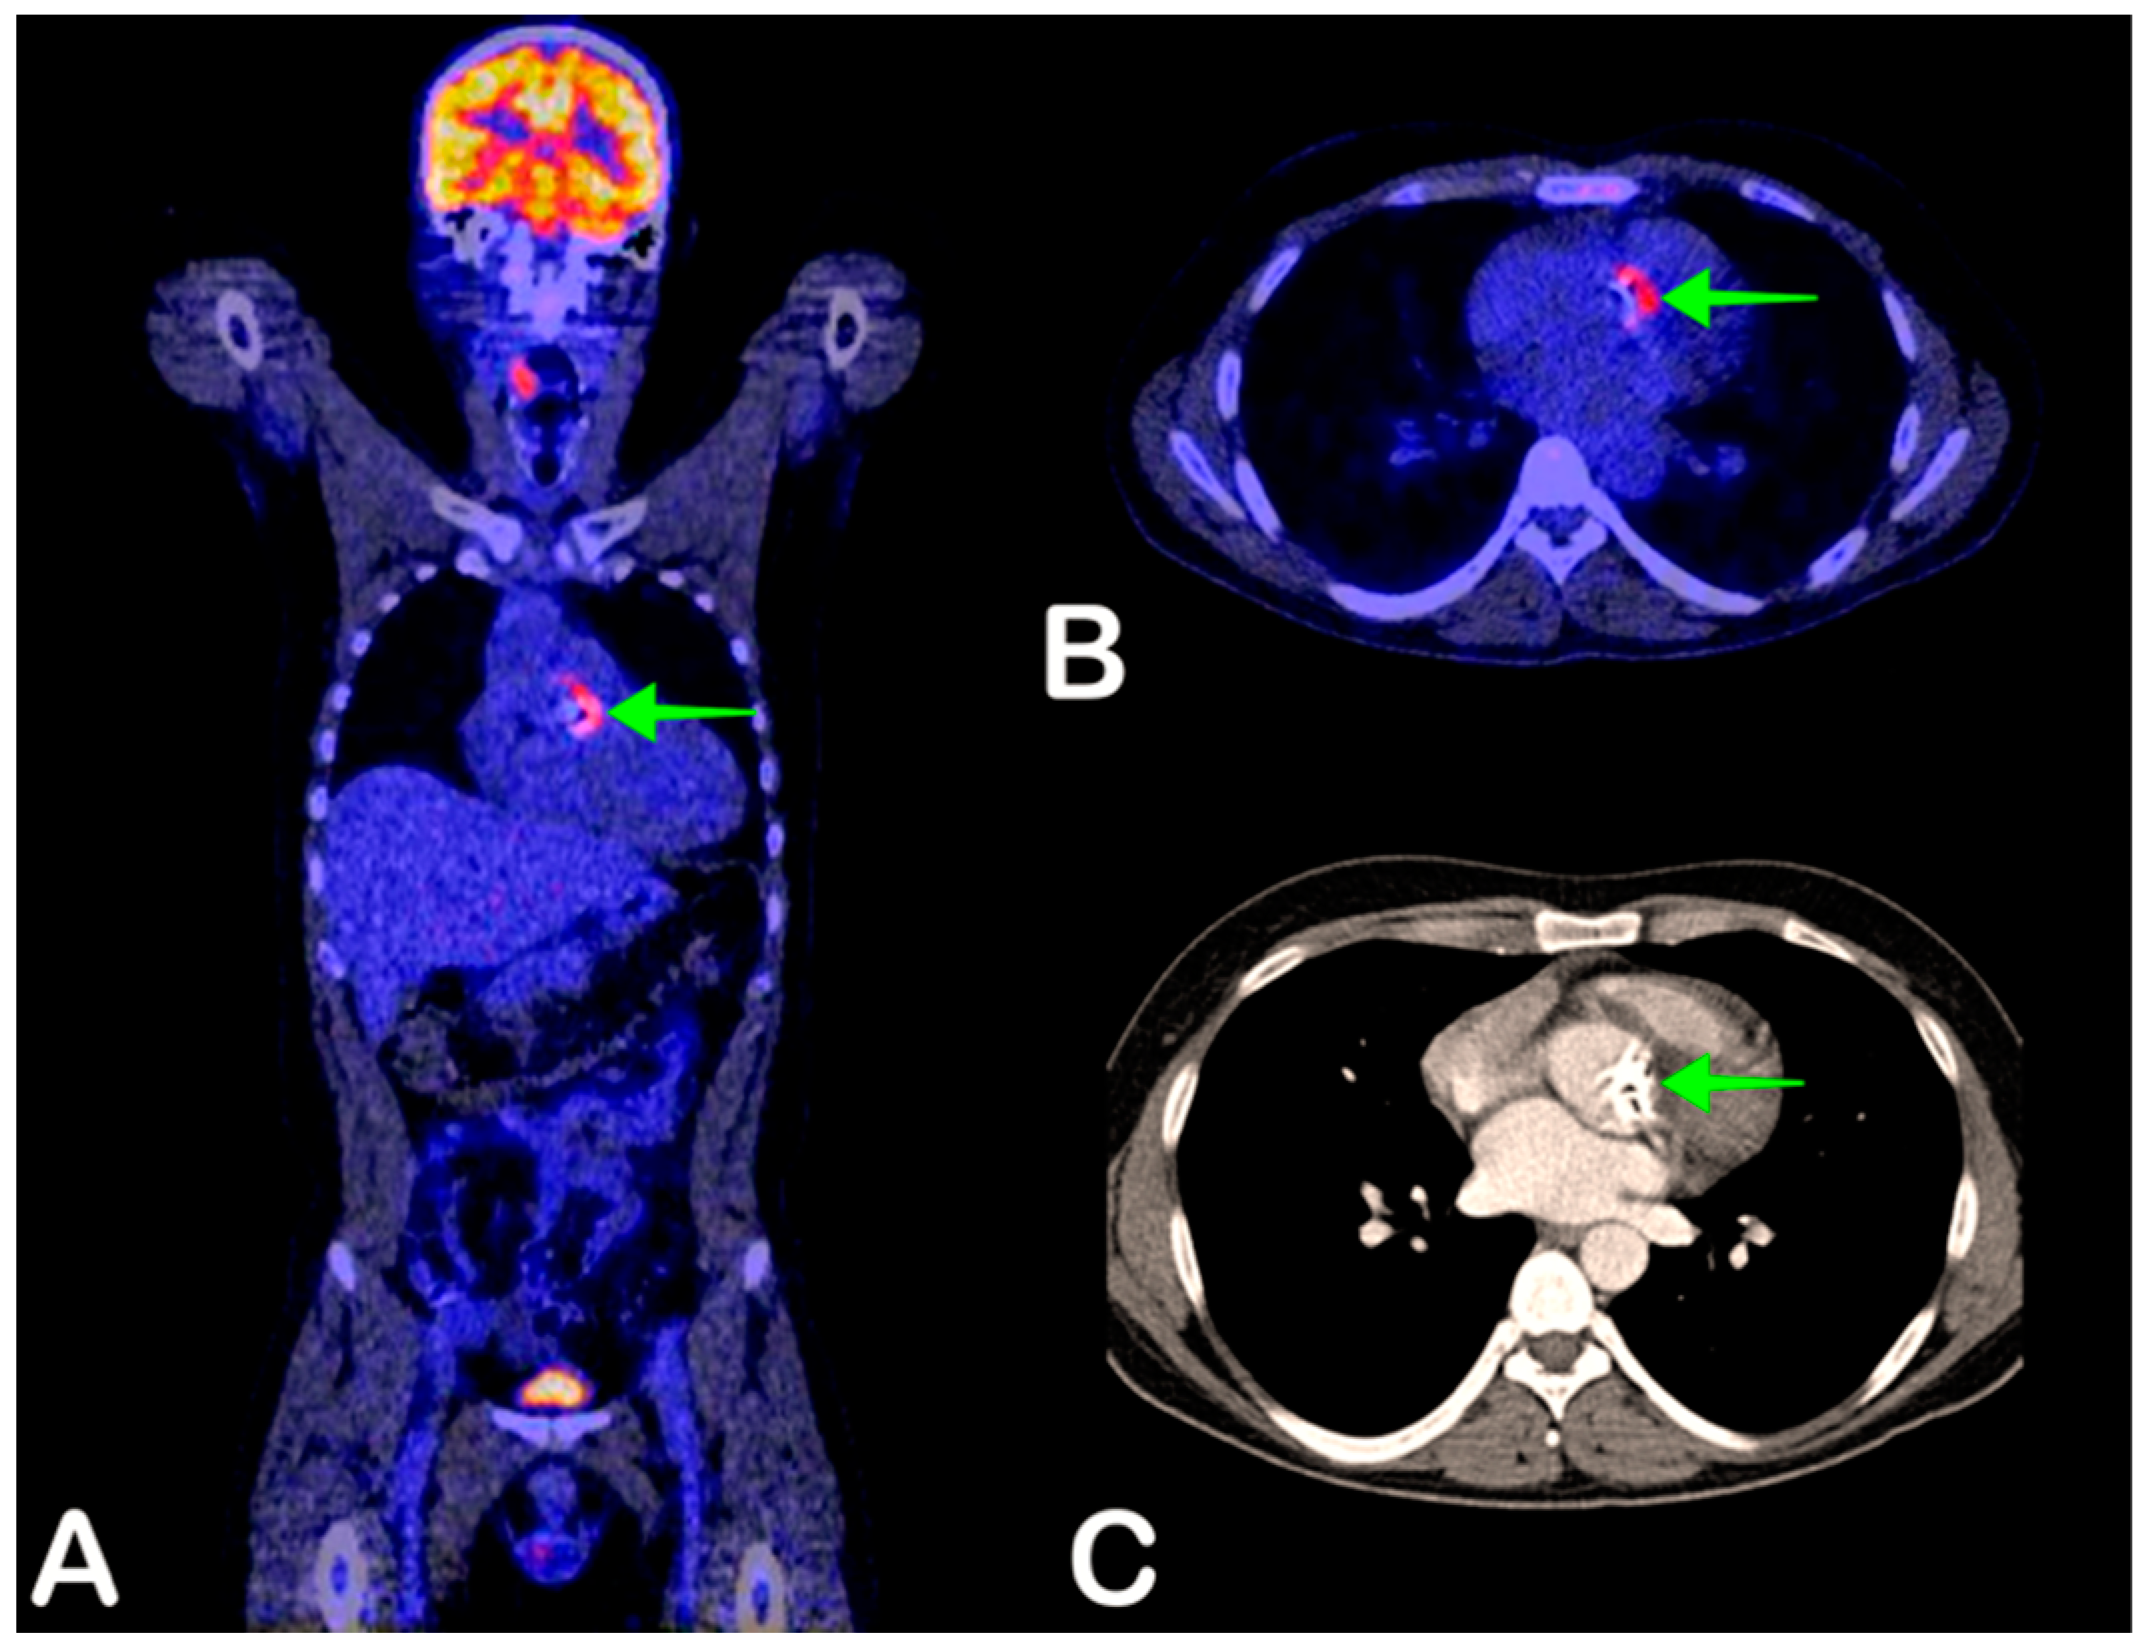

2.3. Infective Endocarditis

- Erba, P.A.; Pizzi, M.N.; Roque, A.; Salaun, E.; Lancellotti, P.; Tornos, P.; Habib, G. Multimodality Imaging in Infective Endocarditis. Circulation 2019, 140, 1753–1765. [Google Scholar] [CrossRef] [PubMed]